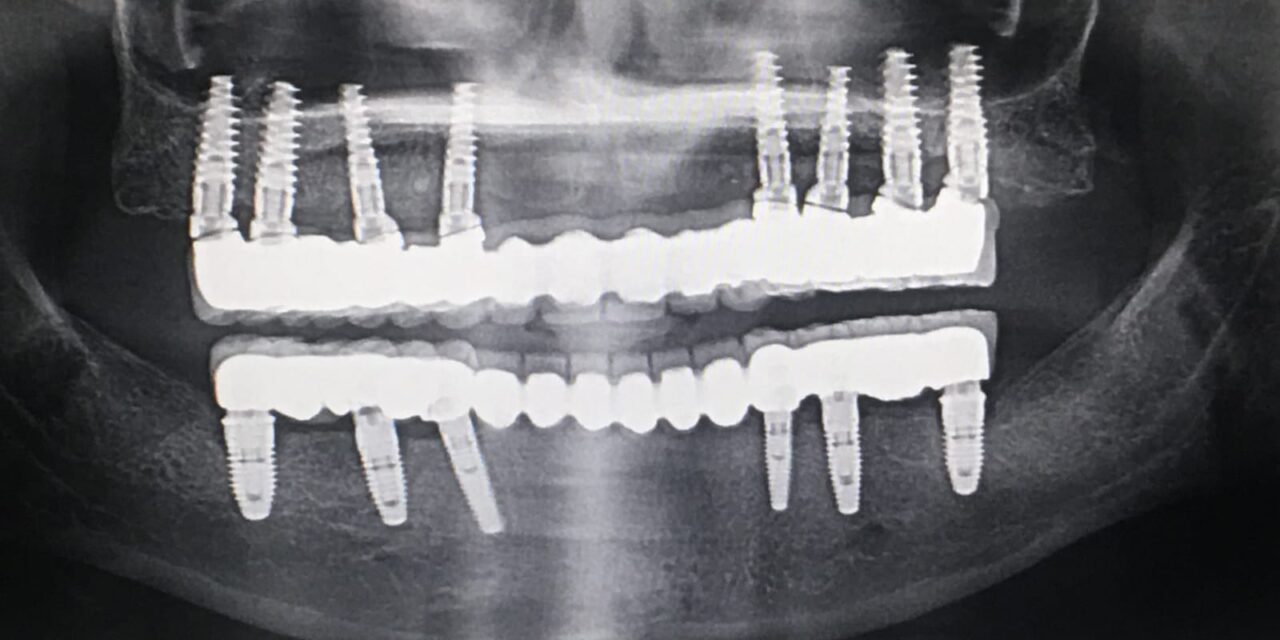

C. Full-Arch Fixed Prosthesis (Full-Arch Bridge / Hybrid Denture)

✪Entire jaw replaced with a fixed prosthesis on multiple implants (usually 4–8).

Common Designs:

All-on-4 / All-on-6 concept

Hybrid prosthesis (metal framework + acrylic/ceramic teeth)

Full zirconia or porcelain bridge

🧩 2. REMOVABLE IMPLANT PROSTHESIS

(Patient can remove it for cleaning, but it’s more stable than a normal denture.)

B. Implant-Supported Overdenture

✪Denture is fully supported by implants, not by gums.

Needs more implants (usually 4–6) and rigid bar structure.

Feels more like a fixed prosthesis but still removable for cleaning.